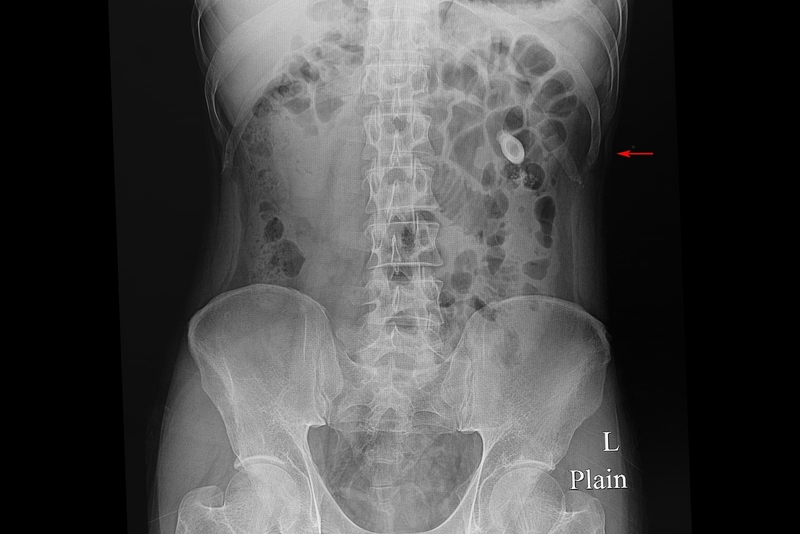

Thông qua kỹ thuật này, bác sĩ có thể nhìn thấy rõ hình ảnh sỏi xuyên qua cơ thể, từ đó biết được kích thước, số lượng, mật độ và vị trí các viên sỏi. Từ đây, bác sĩ sẽ đưa ra phương án điều trị cụ thể dựa trên kết quả chụp và tình hình sức khỏe của bệnh nhân.

Chụp X-quang không dùng thuốc cản quang thường được tiến hành để phát hiện sỏi cản quang đường tiết niệu tại các vị trí: Đài thận, bể thận, bàng quang, niệu đạo, niệu quản. Xác định bóng thận hoặc phân biệt bệnh đau lưng, thắt lưng và vùng xương cụt với đau do sỏi thận, sỏi tiết niệu cũng áp dụng phương pháp này.

Kết quả phim X-quang sỏi thận không cản quang được phân chia tương ứng với các loại sỏi thận như sau: